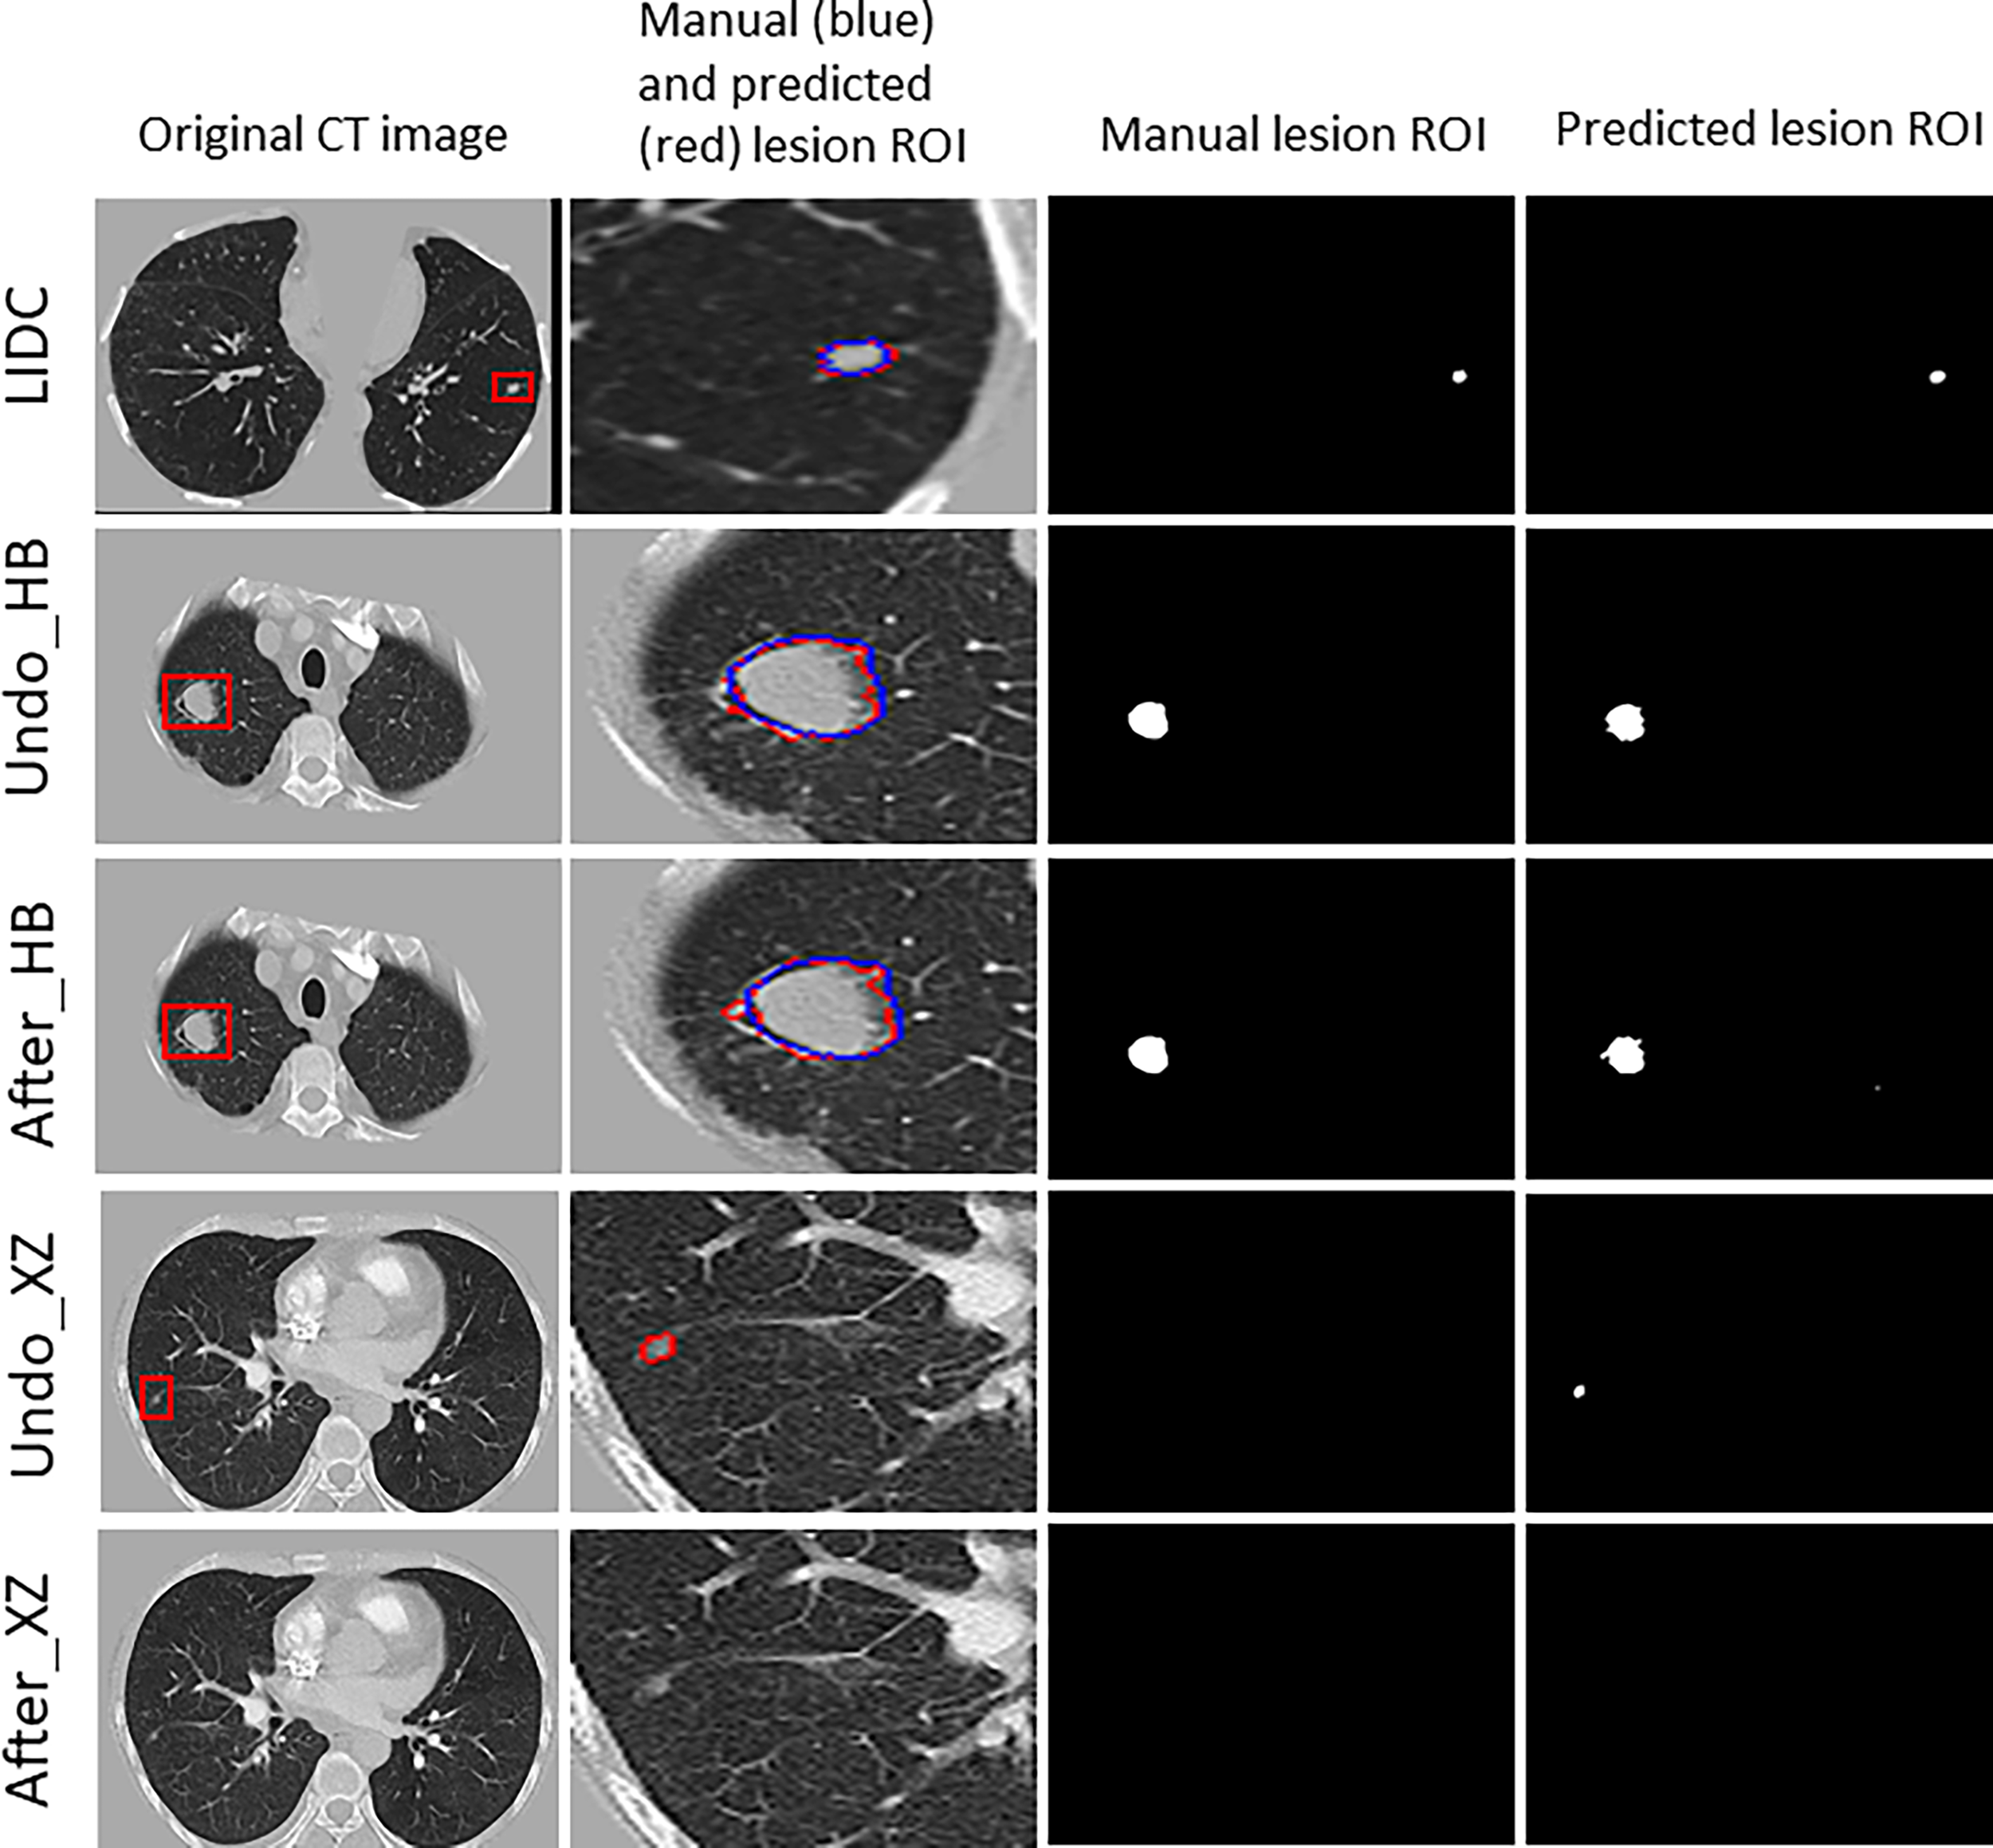

Figure 3 shows examples of segmentation result of the algorithm with and without fine tuning. We observed that the baseline algorithm segmented the lesion region in more details after using the fine tuning method for the HB dataset (i.e., After_HB vs. Undo_HB), which could be reflected by a higher value of ASD that was used to evaluate the algorithms’ edge fitting performance. In addition, it is noteworthy that when the baseline algorithm was applied in XZ dataset, a false positive nodule was detected, but after the algorithm fine tuning the false positive nodule was no longer identified and segmented (i.e., After_XZ vs. Undo_XZ).

Figure 3

The results for example cases before and after using the localized fine tuning method in pulmonary nodules segmentation, and the manually-labeled ROI (blue contour) was compared to segmentation algorithm predicted ROI (red contour).